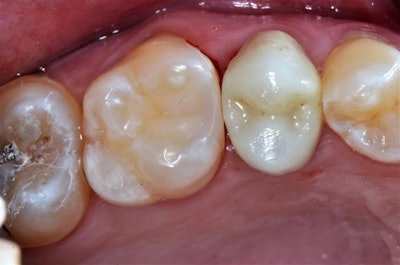

A 30-year-old man presented to the dental practice with a chief complaint of a sensitive tooth on the upper left posterior. Upon examination, the patient's discomfort was found to be due to decay and a leaking old amalgam on tooth #14. A thermal test produced normal results, and a diagnosis of reversible pulpitis was determined.

The clinical objective was to remove the old amalgam and decay and restore the tooth with a composite material, a rather common restorative situation. In this case, Clearfil Majesty ES-2 Universal (Kuraray Noritake Dental) single-shade composite was chosen due to the material's simplicity, ease of use, and ability to blend in with no need for blocker or opaquer in most clinical situations.

The procedure began by isolating the affected tooth from oral fluids using a rubber dam, followed by the mechanical removal of the amalgam and decay as completely, yet conservatively, as possible to maximize tooth structure preservation. Next, removal of the biofilm layer was achieved using a prophy jet handpiece.

A sectional matrix band was placed and the preparation was selectively etched with primer and blue etch for 10 seconds only on the uncut enamel. An immediate dentin sealing technique was performed using Clearfil SE Protect (Kuraray Noritake Dental) according to the manufacturer's instructions for use.

This was followed by a resin coating using Clearfil Majesty ES Flow, then placement of a layer of Clearfil Majesty ES-2 Premium Dentin A2 to cover the dark stain in the dentin. In this type of case, using a darker shade of flowable resin in a dentin shade will easily mask the color and recreate the natural tooth appearance.

A stratification technique was used to restore the tooth by layering the universal composite in approximately 0.5-mm increments, polymerizing each layer with a curing light before applying subsequent layers. The composite used eliminated the need for a blocker shade, streamlining the procedure.

After completing the composite buildup and shaping the occlusal surface, the matrix band was removed for the final cure of the buccal, lingual, and occlusal surfaces. Polishing and finishing was accomplished with a pop-on disc used with a polishing cup and brush.